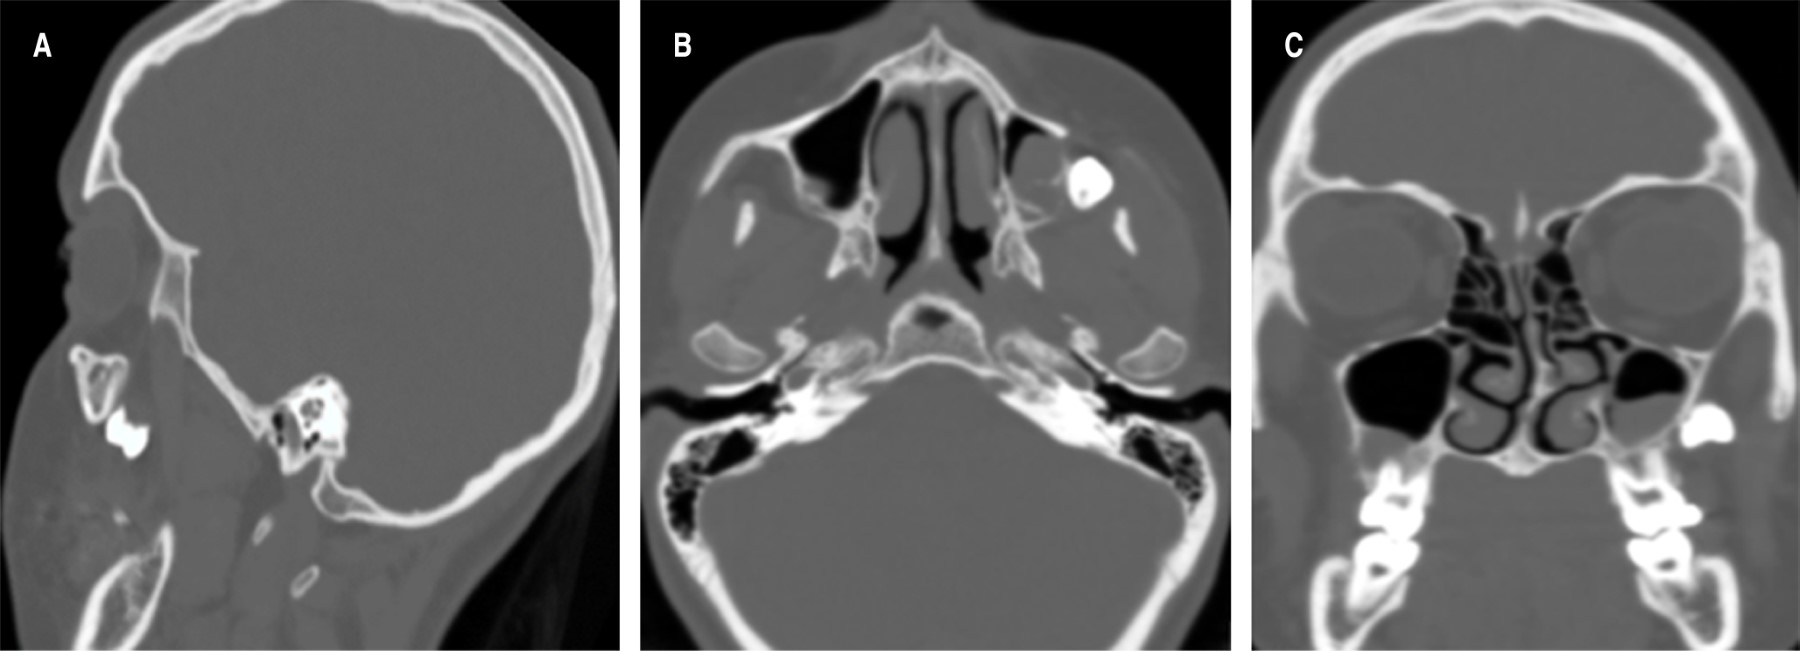

En la evaluación radiográfica postoperatoria, usando una radiografía panorámica se observa la UD 28 en el espacio correspondiente a la fosa pterigomaxilar en una posición transversal según Winter, motivo por el cual se decide realizar una tomografía de haz helicoidal.

Tres semanas posteriores al procedimiento inicial, se realizó evaluación tomográfica en una TC de haz helicoidal, evaluando cortes axiales, coronales, sagitales y reconstrucción volumétrica se pudo observar imagen hiperdensa en relación con la fosa pterigomaxilar compatible con la UD 28 (Figura 3).

Figura 3